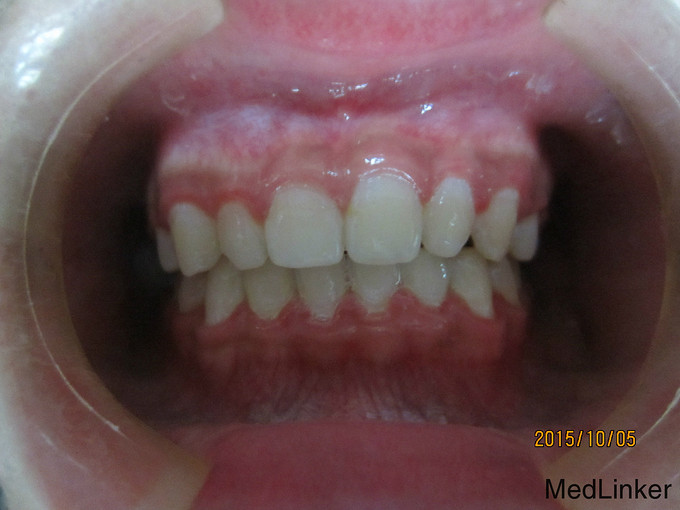

检 查:双侧颞下颌关节开口弹响,开口度一度; 模型测量分析:3度深覆合,上下颌轻度拥挤,spee曲线陡峭,上下颌尖牙尖锐、宽度较小,; 头 颅 侧位片:下颌平面角低角,下颌后缩,余正常; 辅 查:曲面断层片、头颅侧位片,双侧颞下颌关节片

诊断:深覆合、下颌后缩导致颞下颌关节负担加重,引起关节紊乱 治疗:一期:制作合平面导板,戴用一月后关节症状减轻,确定病因; 二期:带用固定矫治器,首先排齐上颌4个月,之后配合平面导板及摇椅弓排齐整平下颌5个月,调整上下颌咬合关系3个月,精细调整2个月,保 持1个月后拆除矫治器,患者自觉关节症状明显好转,制作保持器保持。